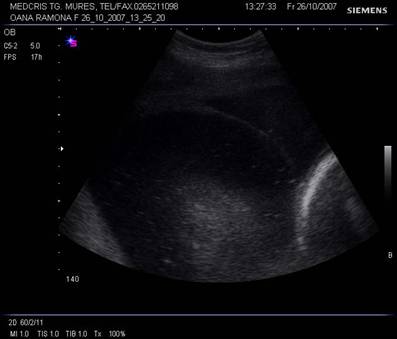

Fig. nr.206. Placenta normal inserata pe peretele anterior uterin , cu marginea sa inferioara la 4 cm de orificiul cervical interin